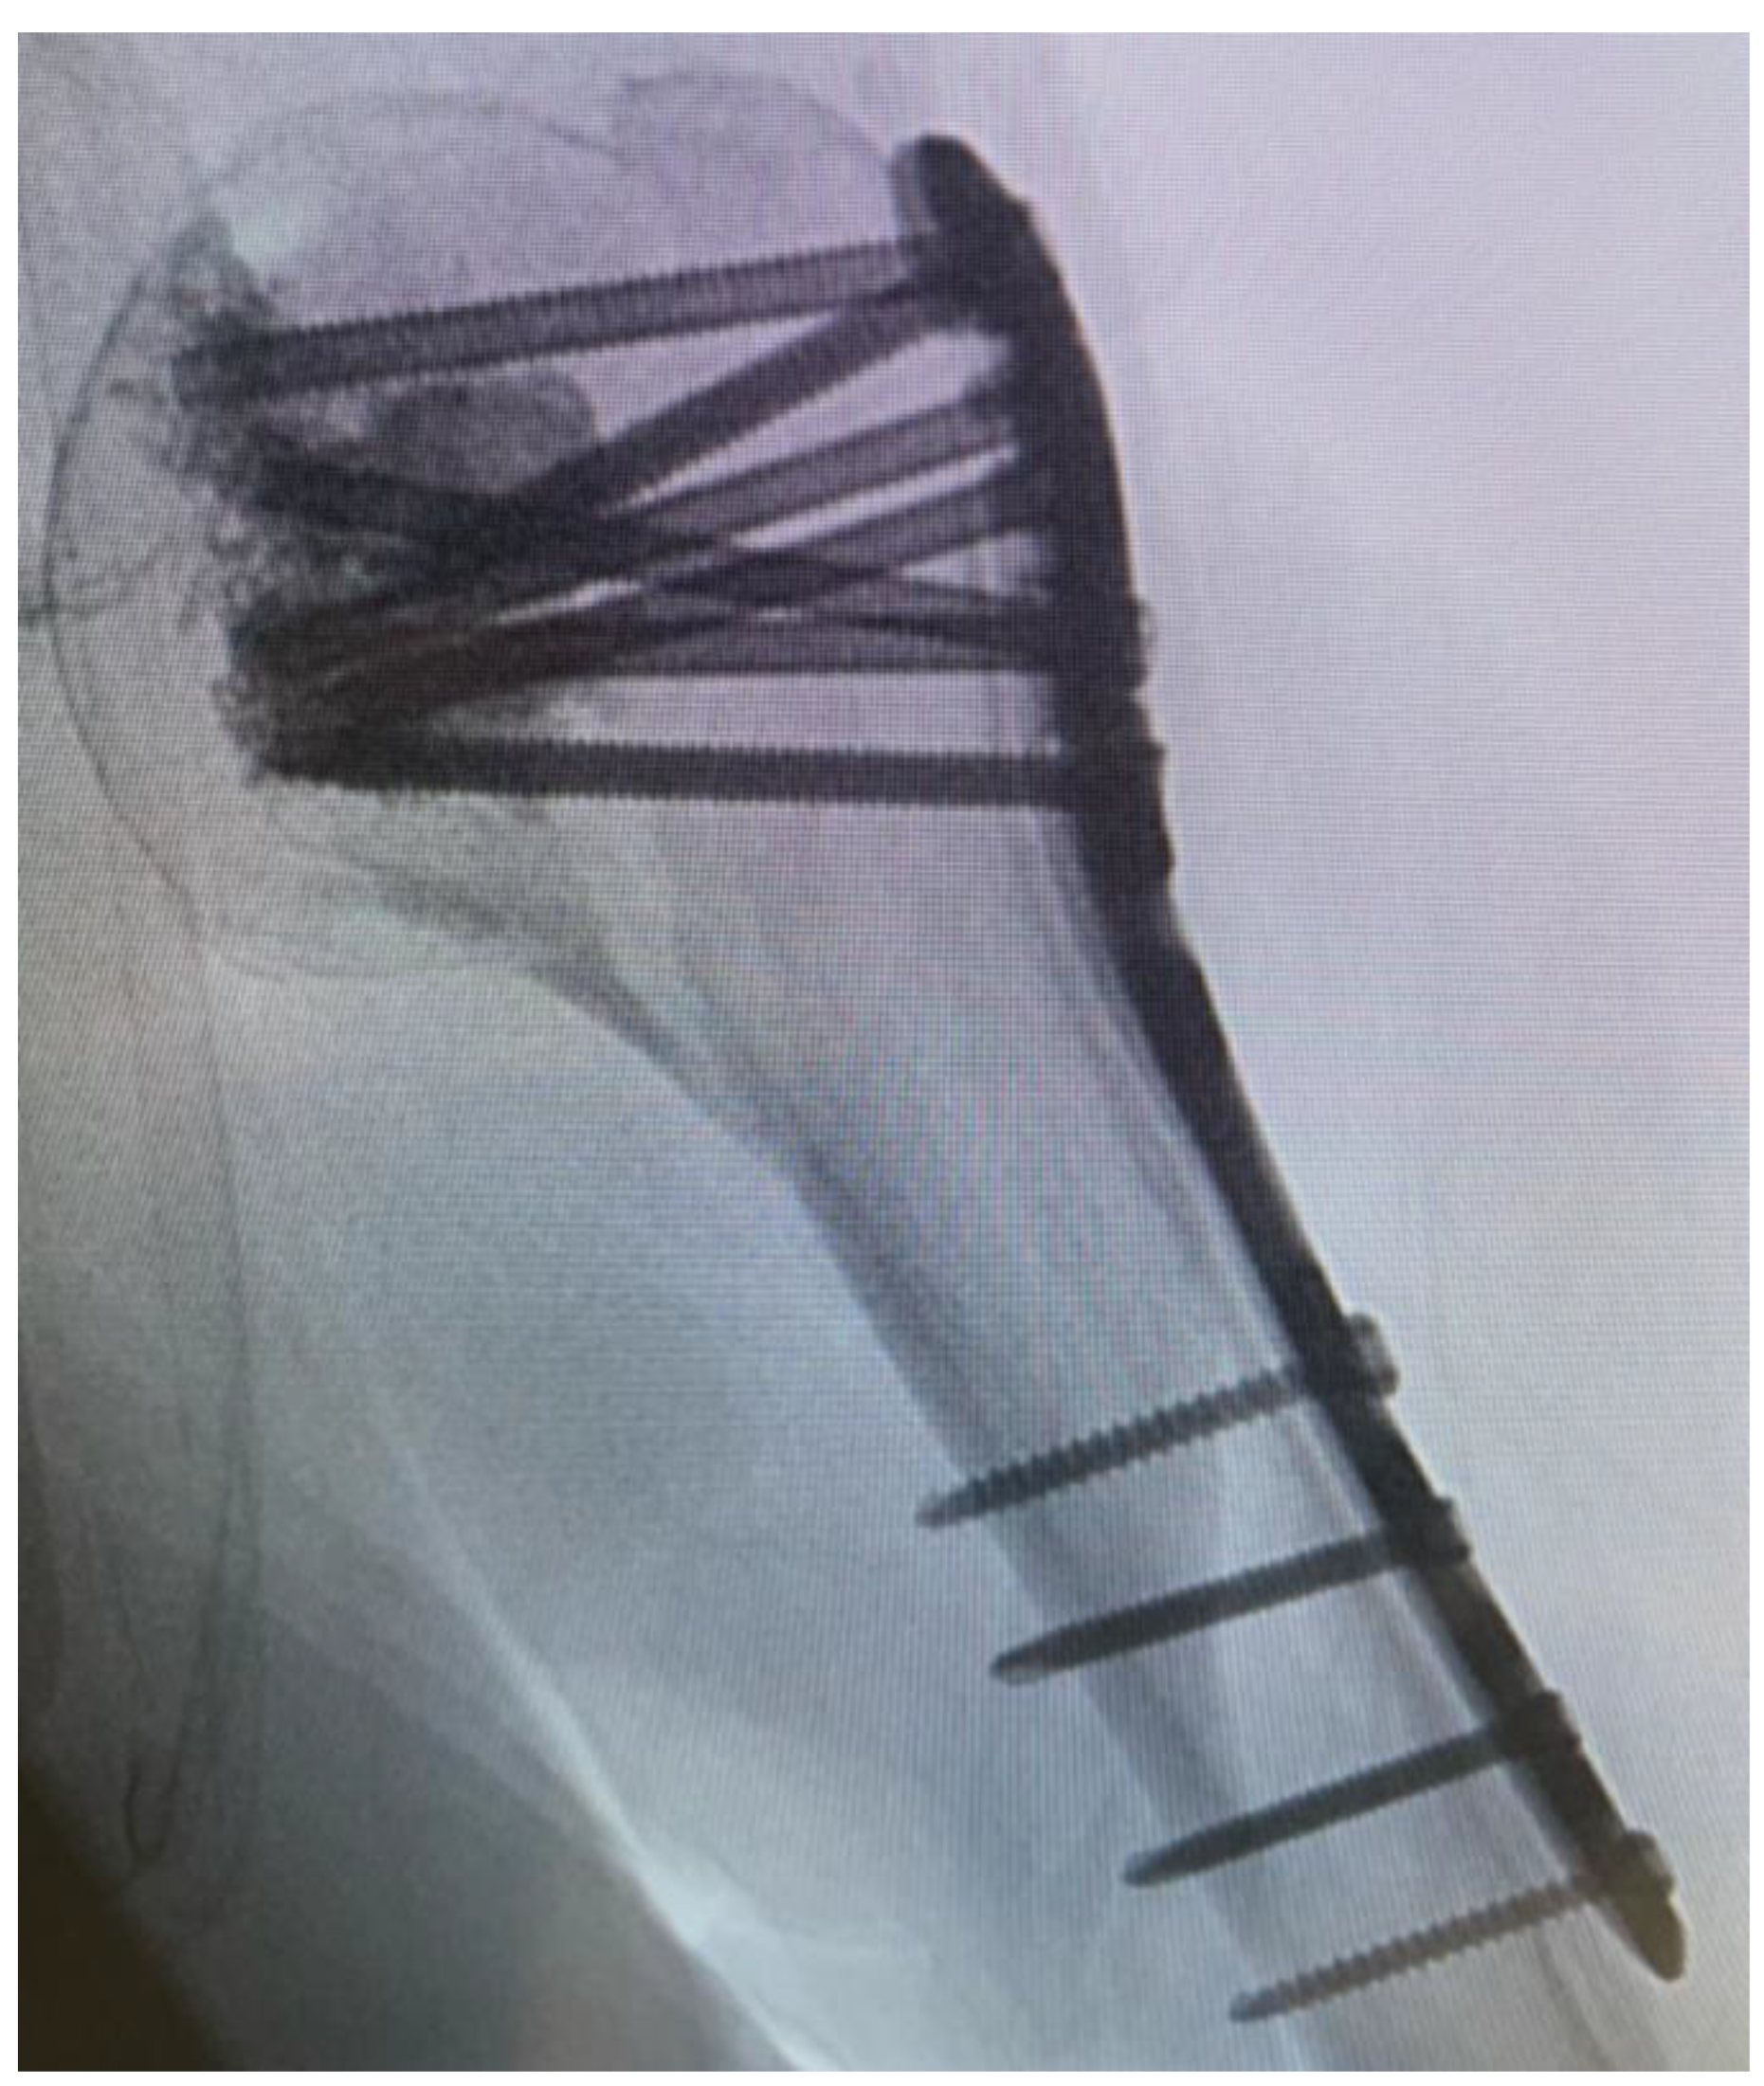

After a minimally invasive delta split procedure, traction sutures were applied through the rotator cuff. A reduction was achieved by the traction and manipulation of the sutures. In some cases, a reduction was achieved by the direct manipulation of the humeral head through the fracture. After a provisional fixation was achieved with 1.6 mm K-wires, the plate was placed and fixed with four to seven screws in the head and three screws in the diaphysis (Figure 2).

After fluoroscopic control of reduction and screw placement, a radiological contrast agent was injected prior to augmentation to prevent leakage into the joint. Afterwards, every screw was augmented with 0.5–1 mL of Traumacem V+ under fluoroscopic control (Figure 3).

Figure 2. Plate placement, temporary fixation with K-wires and implantation of a cortex screw.

Figure 3. Fluoroscopic control after cement augmentation of the screws.